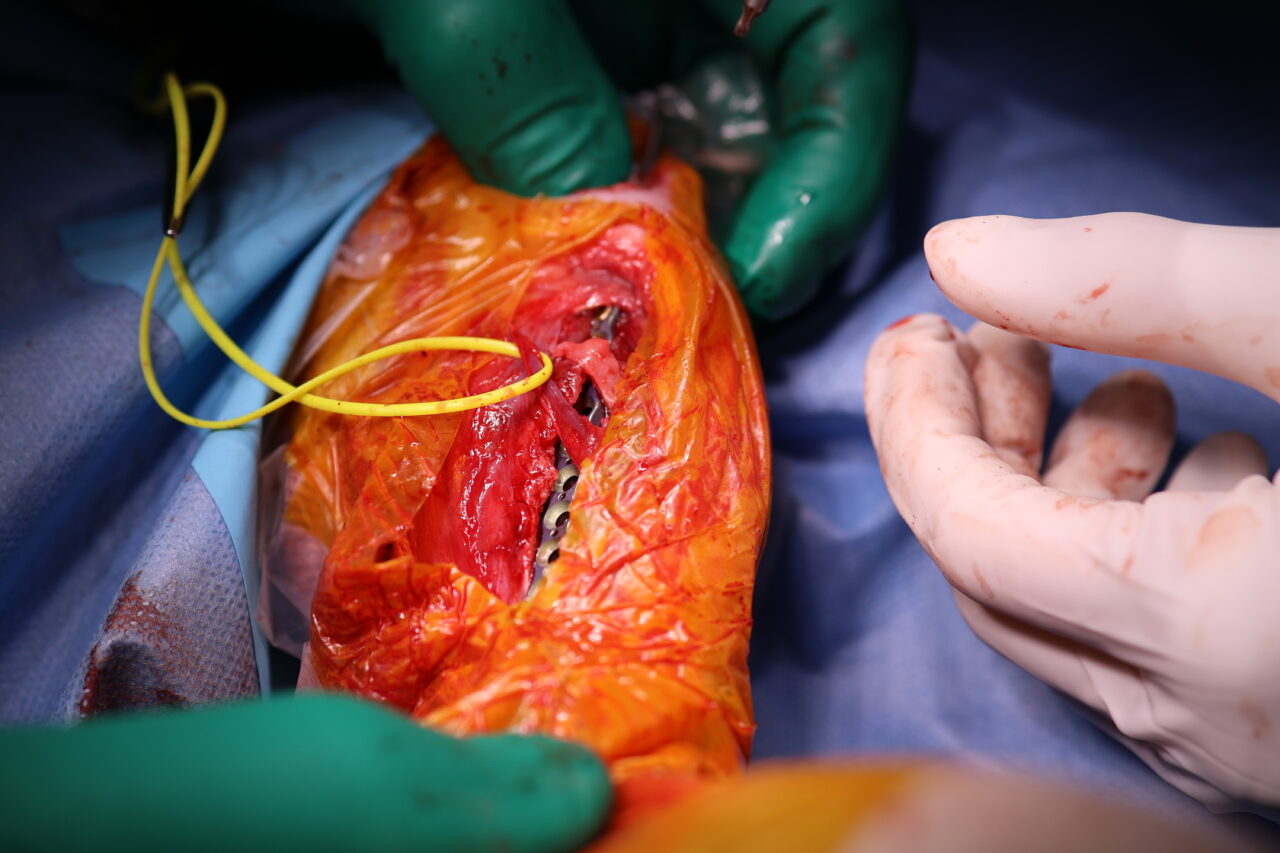

大型の猫に発生した脛骨(すねの骨)骨幹中央部の粉砕骨折 に対してIMピン併用でMIPO法(Minimally Invasive Plate Osteosynthesis) による整復固定術を行いました。

脛骨の粉砕骨折では、

・骨折部の血流温存

・骨癒合環境の維持

・過度な侵襲を避ける

これらが極めて重要になります。本症例ではIMピンで軸方向の支持性を確保し、プレートで回旋・剪断力を制御することで、骨折部をほとんど展開せずに安定性を確保しました。

MIPO法は骨折周囲の軟部組織を温存できる一方で、正確なアライメント管理と固定設計が求められる手技です。術後X線ではアライメントは良好で、固定バランスも安定しています。今後は仮骨形成と骨癒合の経過を慎重にフォローしていきます。